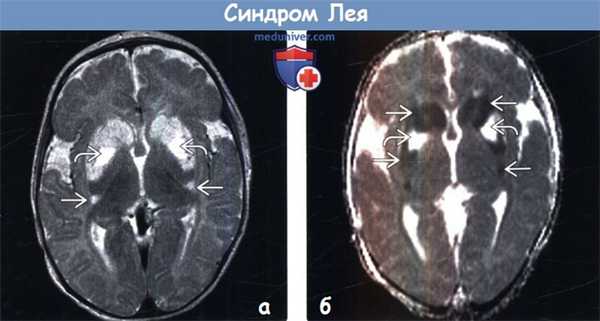

(а) МРТ, Т2-ВИ FSE, аксиальный срез: у младенца с гипотонией и энцефалопатией определяется повышение интенсивности сигнала от головок хвостатых ядер и скорлупы. Обратите внимание на вовлечение наиболее задних отделов скорлупы. Центральные отделы скорлупы характеризуются гиперинтенсивным сигналом.

(б) МРТ, карта ИКД, аксиальный срез: у того же пациента определяется ограничение диффузии в области головок хвостатых ядер и большей части пораженной скорлупы билатерально, тогда как центральные отделы скорлупы характеризуются повышенным коэффициентом диффузии что указывает на предшествующее кавитирующее поражение.